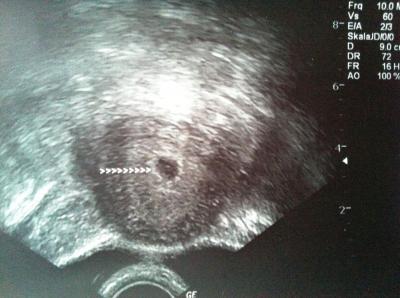

Für meinen 1.FA-Termin hatte ich ja jetzt nicht so hohe Erwartungen, weil ich ja hier schon viel mitgelesen hab. Es war trotzdem sehr nett. Die ganzen grundlegenden Sachen (Impfungen, Ernährung (2 Tassen Kaffee/Tag sind okay), Ablauf und so weiter) wurden besprochen und untersucht wurde ich natürlich auch. Hier ist ein Foto: Okay, ist jetzt nicht so spektakulär, aber ich bin trotzdem stolz wie Bolle 5 mm groß und alles so wie es sein sollte (bei 5+1). Jetzt soll ich in 3 Wochen wieder kommen.

nicht spektakulär? hey das ist das Bild das das ganze Leben auf den Kopf stellt :-) ich fand genau dieses Bild bei mir damals in der ersten ss auch suuuper sensationell, war da übrigens auch 5+1. jetzt warte ich ja noch auf das tolle Foto :-D wie cool das dein Arzt so Sachen wie Ernährung mit dir bespricht. die meisten nehmen sich dafür ja keine Zeit :-(

Schönes Bild für 5+1!

Das ist ja ein super schönes Foto geworden, hoffentlich krieg ich morgen auch so gute Nachrichten!

Sieht super aus das Bild! Ein erstes Foto von deinem Kind! Herzlichen Glückwunsch!